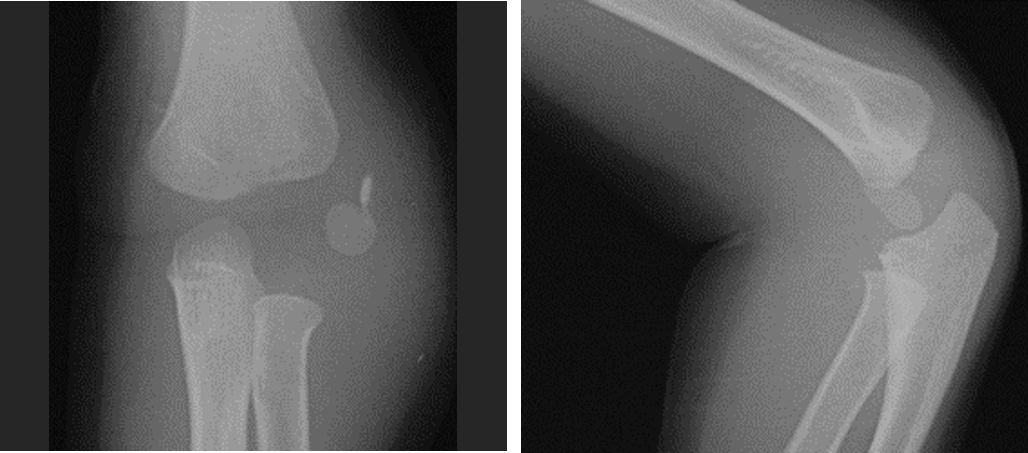

肘頭骨折 抜釘手術後7日目 卒業 入院 肘頭骨折、卒業しました! 昨年8月に、自転車走行中に転倒し肘頭骨折。 入院&手術 (日間)を経てリハビリを続け、先月3月25日に抜釘手術 (ボルト抜き)のために再び入院しました。 幸い26日に行われた手術は特に問題もなく、経過は順調。 抜釘手術直後は、再び肘 肘頭骨折 抜釘手術後7日目 卒業さらに肘も診察します( 診断 診断 骨折は、骨がひび割れたり折れたりすることです。ほとんどの骨折の原因は、骨に力がかかることです。 通常、骨折はけがや酷使によって発生します。 損傷した部位には痛みが生じ(特にその部位を使うとき)、通常は腫れ上がります。また、あざ、ゆがみや曲がり、ずれなどがみられることがあります。 肘 の骨折は骨折の中でも 結構厄介な骨折 で、 特にリハビリテーションがなかなか順調にいかないことが多い 骨折です。 間違ったリハビリをしてしまうと、逆に肘がカタくなってしまって、余計に曲がらなくなったり、伸びなくなったり、痛みが増したりしてしまいますので、 大切なポイントを押さえながら、かつ、同じ曲げる、伸ばすでも様々な

桡骨 肘 骨折- 肘をついて転倒すると骨折しやすい「肘頭」という部分があります。 読み方は 肘頭骨折 「 ちゅうとうこっせつ 」です。 この肘頭部の骨折では手術後のリハビリが上手くいかず、 肘の関節が固まって動かなくなる事が非常に多い場所 です。 まず、腕や肘、足で大きく違うのは、足には体重がかかる場所ということです。 なので、骨折の治癒過程はおおよそ同じなのですが治療期間が変わってきます。 ではどのぐらいの治療期間が変わってくるかといいますと 約1~2か月 変わってきます。

肘頭骨折 一般社団法人 日本骨折治療学会 骨折の解説